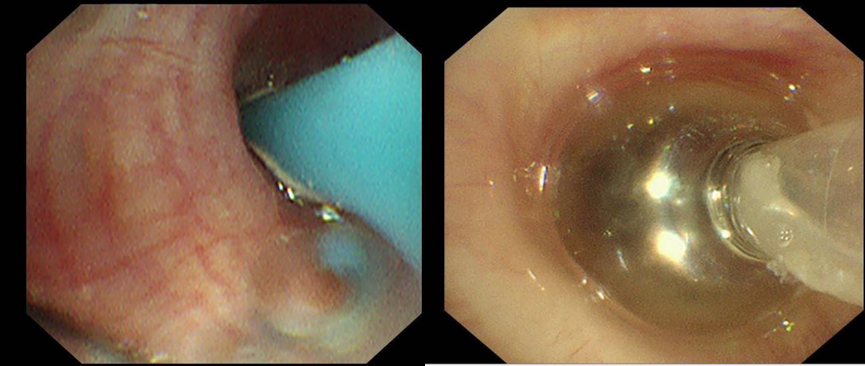

首次检查中,团队运用Chartis测压技术,对右上叶、右中间支气管进行测压,判断漏气位于右上叶。再对右上叶后段、前段、尖段测压后,见右上叶尖段漏气,随着负压加大,吸气压曲线明显,反复测试多次见右上叶尖段漏气减少明显,考虑持续漏气的部位是右上叶尖段。同时,于右上叶尖段予球囊扩张导管进一步堵塞,胸腔负压引流瓶未见明显气泡漏出,进一步证实右上叶尖段漏气。Chartis测压技术如同给气道做“精准导航”,成功定位右上叶尖段为漏气部位。这一关键发现,为后续治疗奠定基础,明确了“补漏”的目标靶区。

出院前复查气管镜于右上叶尖段见活瓣开口,局部予充分灌洗后未见气泡溢出,复查胸片提示右侧气胸较前明显吸收好转,困扰患者许久的胸腔闭式引流瓶终于得以拔除,王女士彻底告别了支气管胸膜瘘带来的阴霾。曾经,沉重的胸腔闭式引流瓶如影随形,严重限制了她的行动,如今,她终于能够轻松自在地行走。所使用的支气管内活瓣治疗也已纳入苏州医保,减轻了她的经济负担。出院之际,王女士难掩内心的感激流下了泪水,她紧紧握着蒋军红主任的手,言辞恳切地说到:“在患病的这段艰难日子里,是你们精湛的医术和无微不至的关怀,给了我重新生活的希望。每一次治疗,我都能感受到整个医疗团队的全力以赴。从病情诊断,到治疗方案的制定与实施,每一个环节都严谨细致,感谢蒋主任及各位医护人员。”